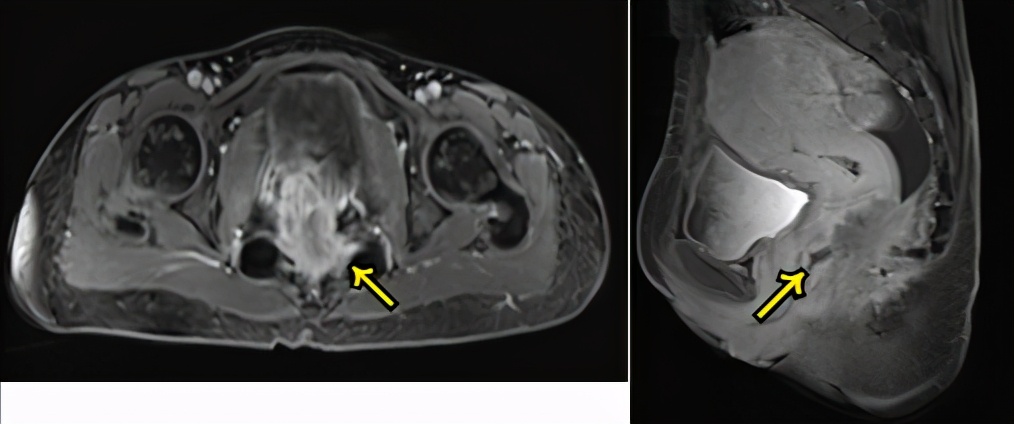

治疗结束后随访MRI(2021.5):肿瘤基本消退,阴道形态恢复正常